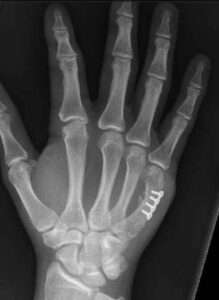

See below the two treatment approaches for a patient who has metacarpal fracture.

Fig 2: Action Rehab Treatment

Your Action Rehab hand therapist will fabricate a custom thermoplastic splint which will allow for healing and union of the fracture, followed by an array of ranging and stability exercises. The primary goals of treatment are to achieve acceptable alignment, stable reduction, strong bony union, and unrestricted motion.